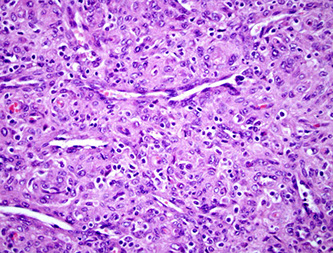

Sinonasal Undifferentiated Carcinoma (SNUC)

IHC: (+) LMWK, p63 (patchy)

- neg: SYN (1/4+), EBV,

Sinonasal undiff carcinoma c lobular growth pattern

Undifferentiated (anaplastic) ca are very aggressive (very poor px), have nests, sheets, and trabeculae